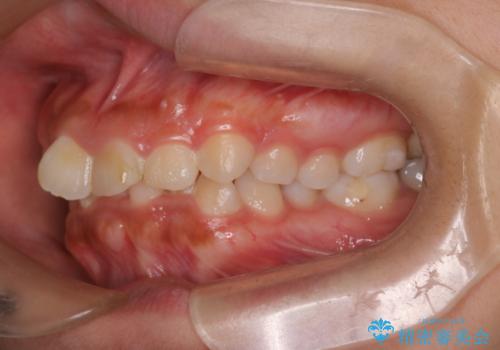

- 歯のデコボコ(叢生)を気にされて来院されました。精密な検査の結果、中等度の叢生と診断。患者様のご希望に合わせ、透明で目立ちにくい**インビザライン(マウスピース矯正)**による治療計画を立案しました。歯を抜かずに、歯列弓(歯が並ぶアーチ)を少しずつ拡大することで、歯が並ぶスペースを確保し、叢生を改善することを目指します。

今回の矯正治療では、透明なマウスピース型の装置インビザラインを使用しました。この装置は目立ちにくく、取り外しが可能なため、食事や歯磨きも普段通りに行えます。治療は、緻密に計算された治療計画に基づき、段階的に作製されたマウスピースを交換していくことで、歯列弓全体を徐々に広げていきました。この歯列弓の拡大により、不足していたスペースを確保し、歯のデコボコを効果的に解消。抜歯することなく、整った美しい歯並びと良好な咬み合わせを獲得していただけました。